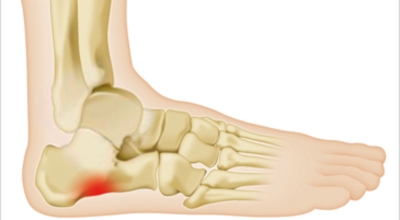

족저 근막이란 발가락 시작지점부터 발뒤꿈치뼈까지 발바닥 전체를 감싸고 있는 두꺼운 막을 말해요. 족저 근막은 발바닥 아치를 지속시켜 발바닥이 지면을 내딛음으로써 나타나는 충격을 흡수하는 중요한 역할을 수행하고 있어요. 이 족저 근막에 일차적으로 서서히 조직 손상이 일어나고 계속적인 활동으로 인해 염증이 커지면서 발 뒤꿈치 부근 통증을 유발하게 되는데 염증은 무리하고 반복적인 동작, 과도한 사용으로 마찰에 의해 발생해요.